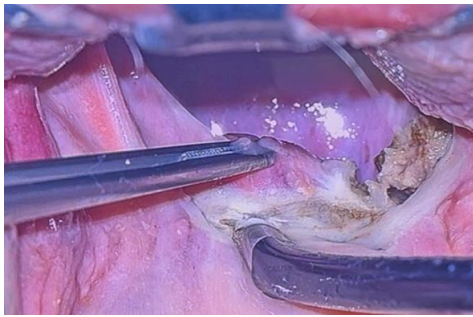

This leads to a stable repositioning of the posterior pillar to more lateral and anterior location without any knot, then this stitch is repeated at least three times between raphe and muscle till the lower pole of the muscle is reached. The opposite side is done by the same way. Finally, cach thread comes out at the raphe of the same side, for locking of the stitches and looseness prevention; a superficial stitch in the opposite direction is taken, and then the thread is cut while bushing the tissue downward for more traction

Figure 2